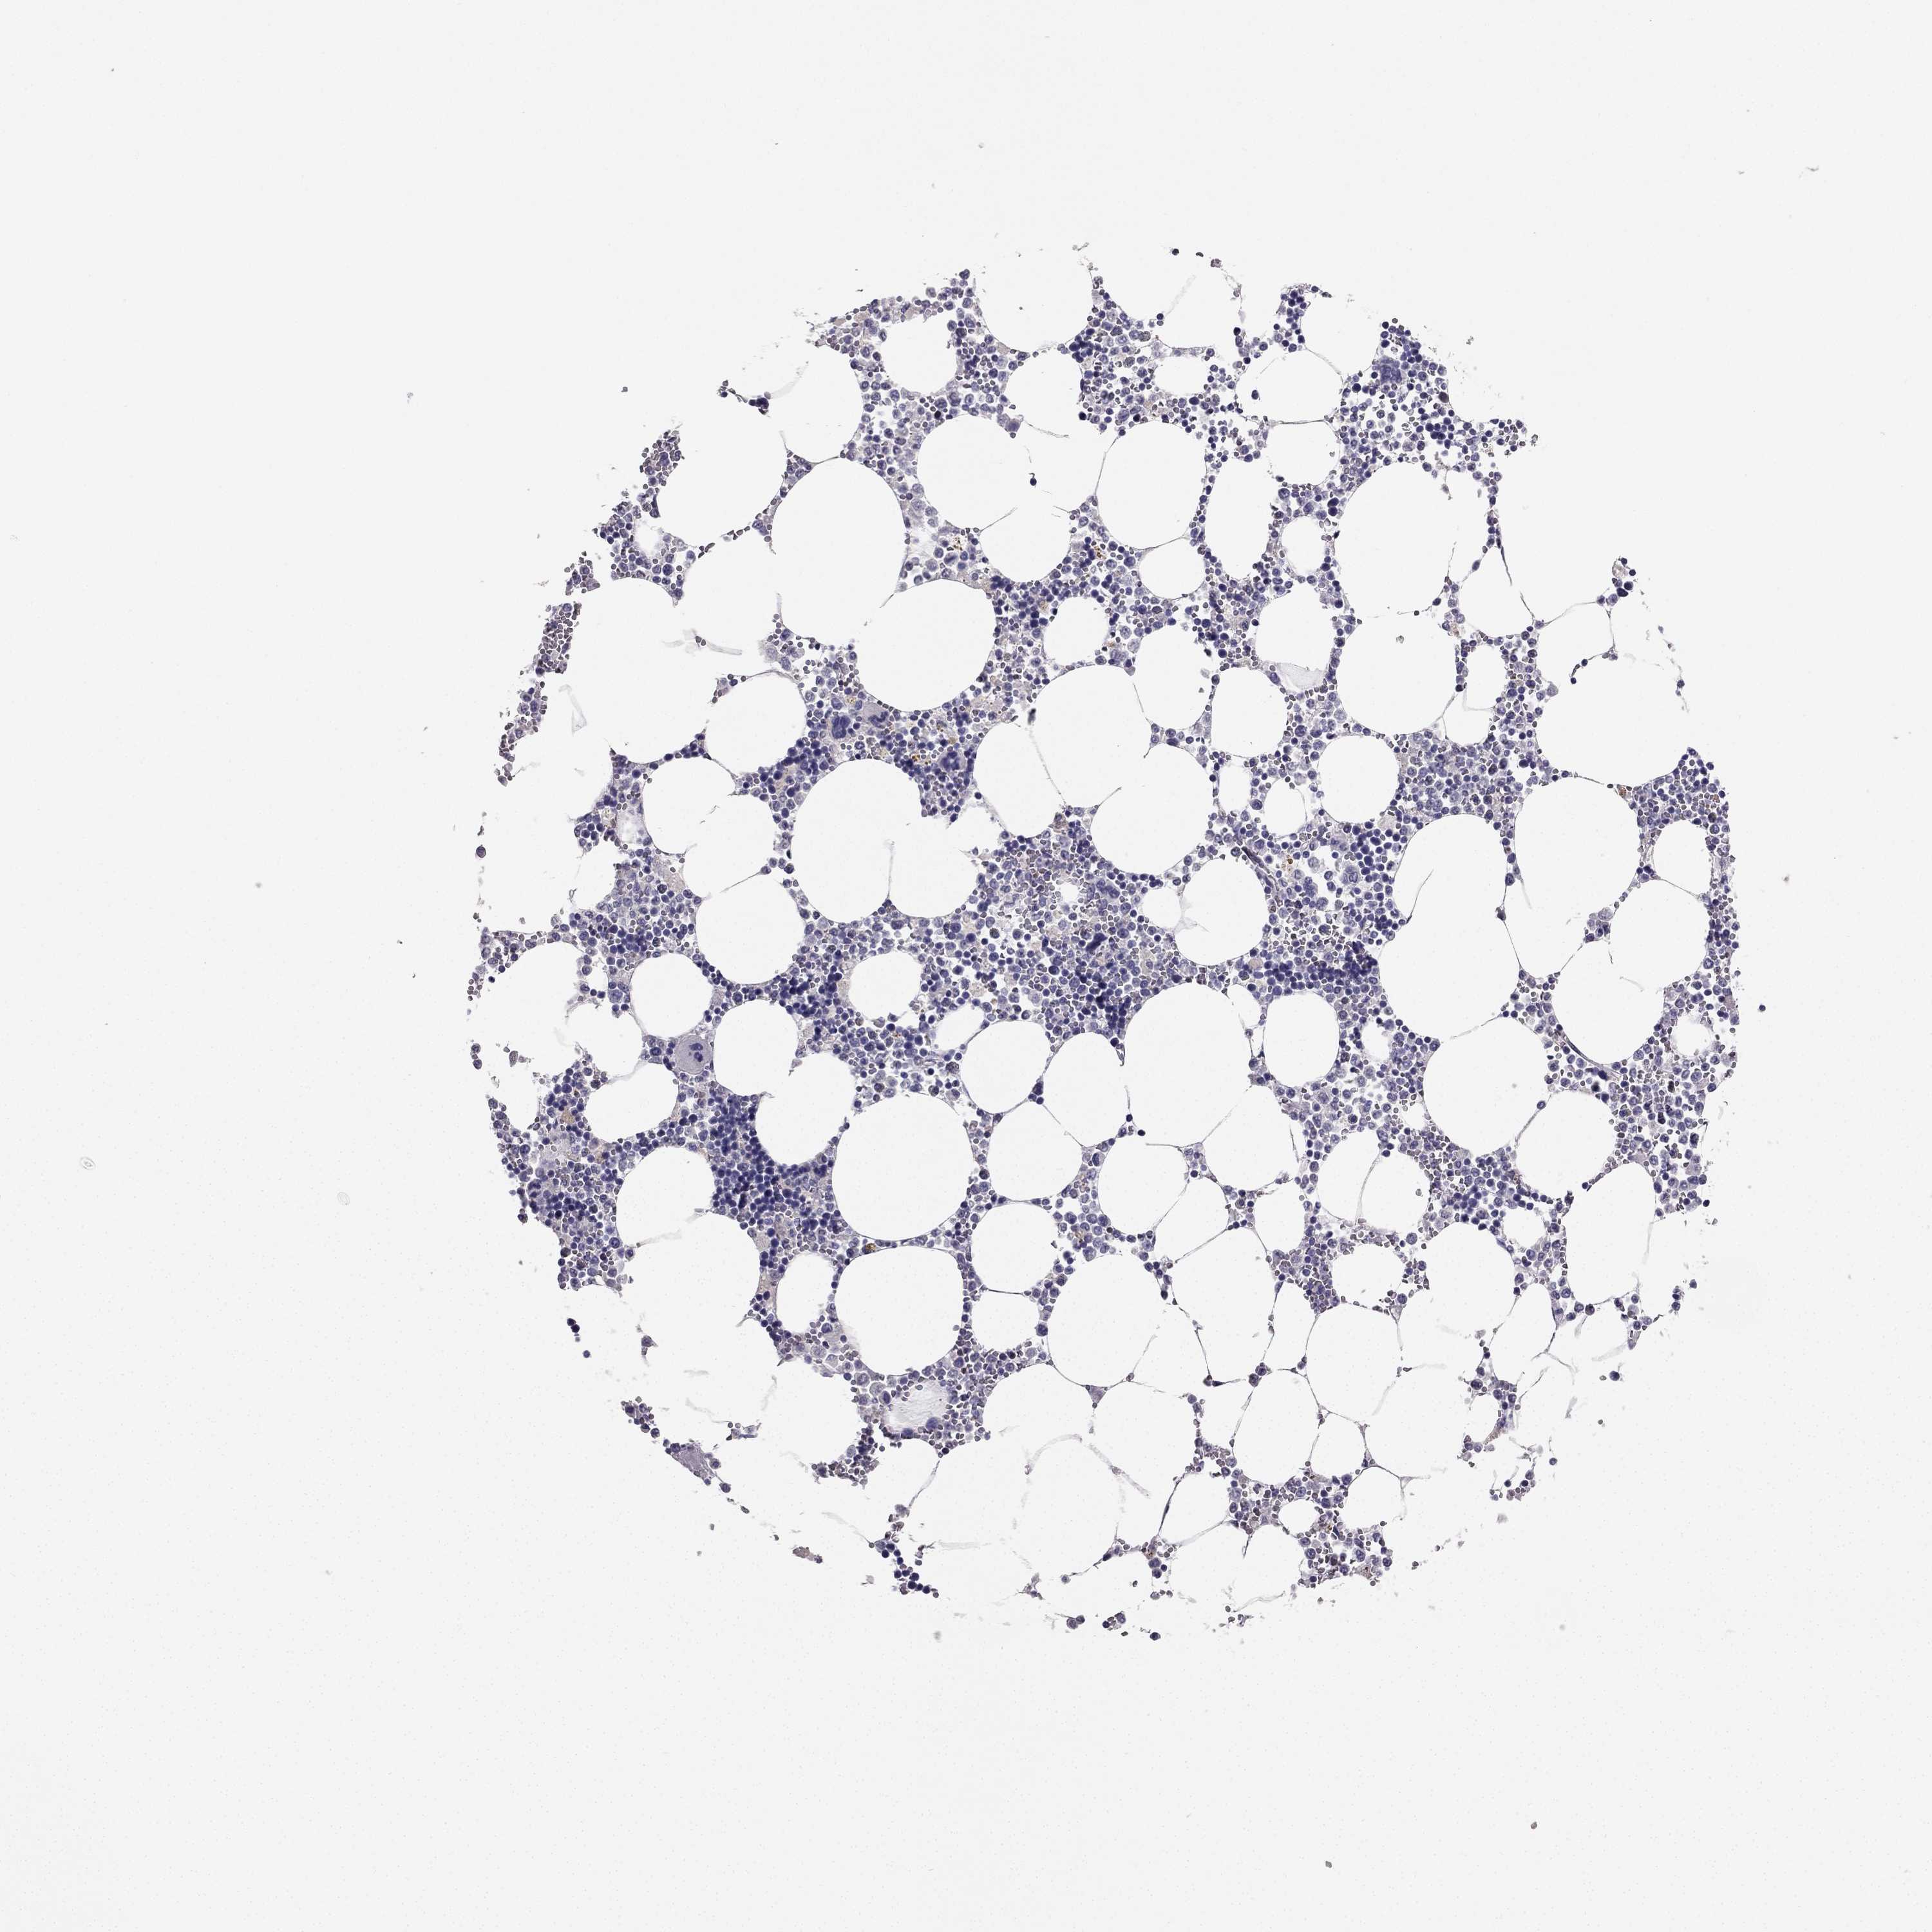

BONE MARROW - Antibody stainingi

Antibody staining in the annotated cell types in the current human tissue is reported as not detected, low, medium, or high, based on conventional immunohistochemistry profiling in selected tissues. This score is based on the combination of the staining intensity and fraction of stained cells.

Each image is clickable and will lead to virtual microscopy that enables deeper exploration of all samples and also displays staining intensity scores, fraction scores and subcellular localization as well as patient and tissue information for each sample.

Antibody HPA007305Antibody HPA007306Antibody CAB000106

Hematopoietic cells LowLowNot detected